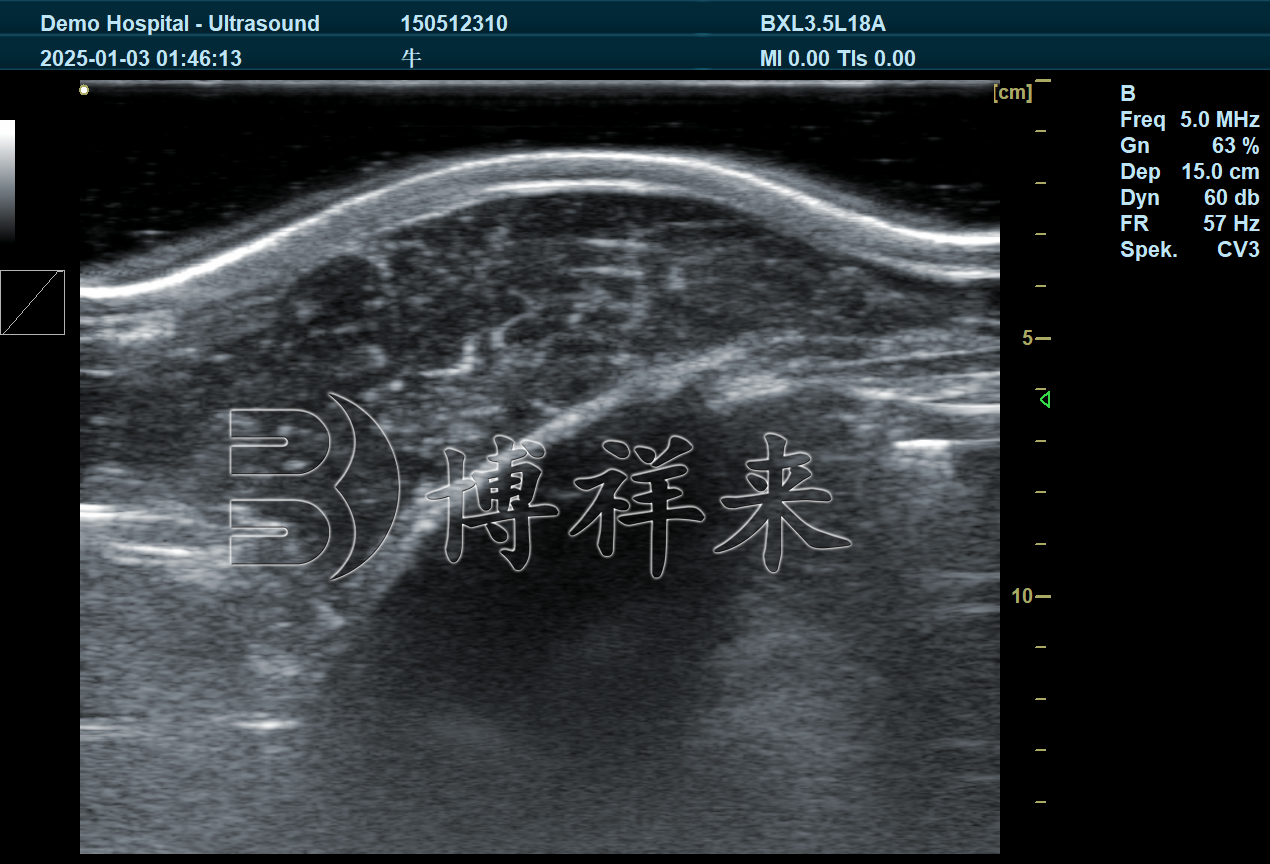

三、博祥来背膘眼肌测定仪BXL-DB20的技术突破

针对以上行业难题,博祥来新一代背膘眼肌测定仪实现了关键技术升级:

1. 128阵元18cm大探头:真正“打全眼肌”

探头长度:18cm

阵元数量:128阵元

扫描深度:**30cm

优势:

完整覆盖大体重肉牛眼肌

即使1000kg以上牛只也能一次成像

避免拼接误差

2. 高穿透+高清成像:解决“看不清”的问题

深层组织清晰显示

肌肉与脂肪层分界明显

轮廓边界清晰